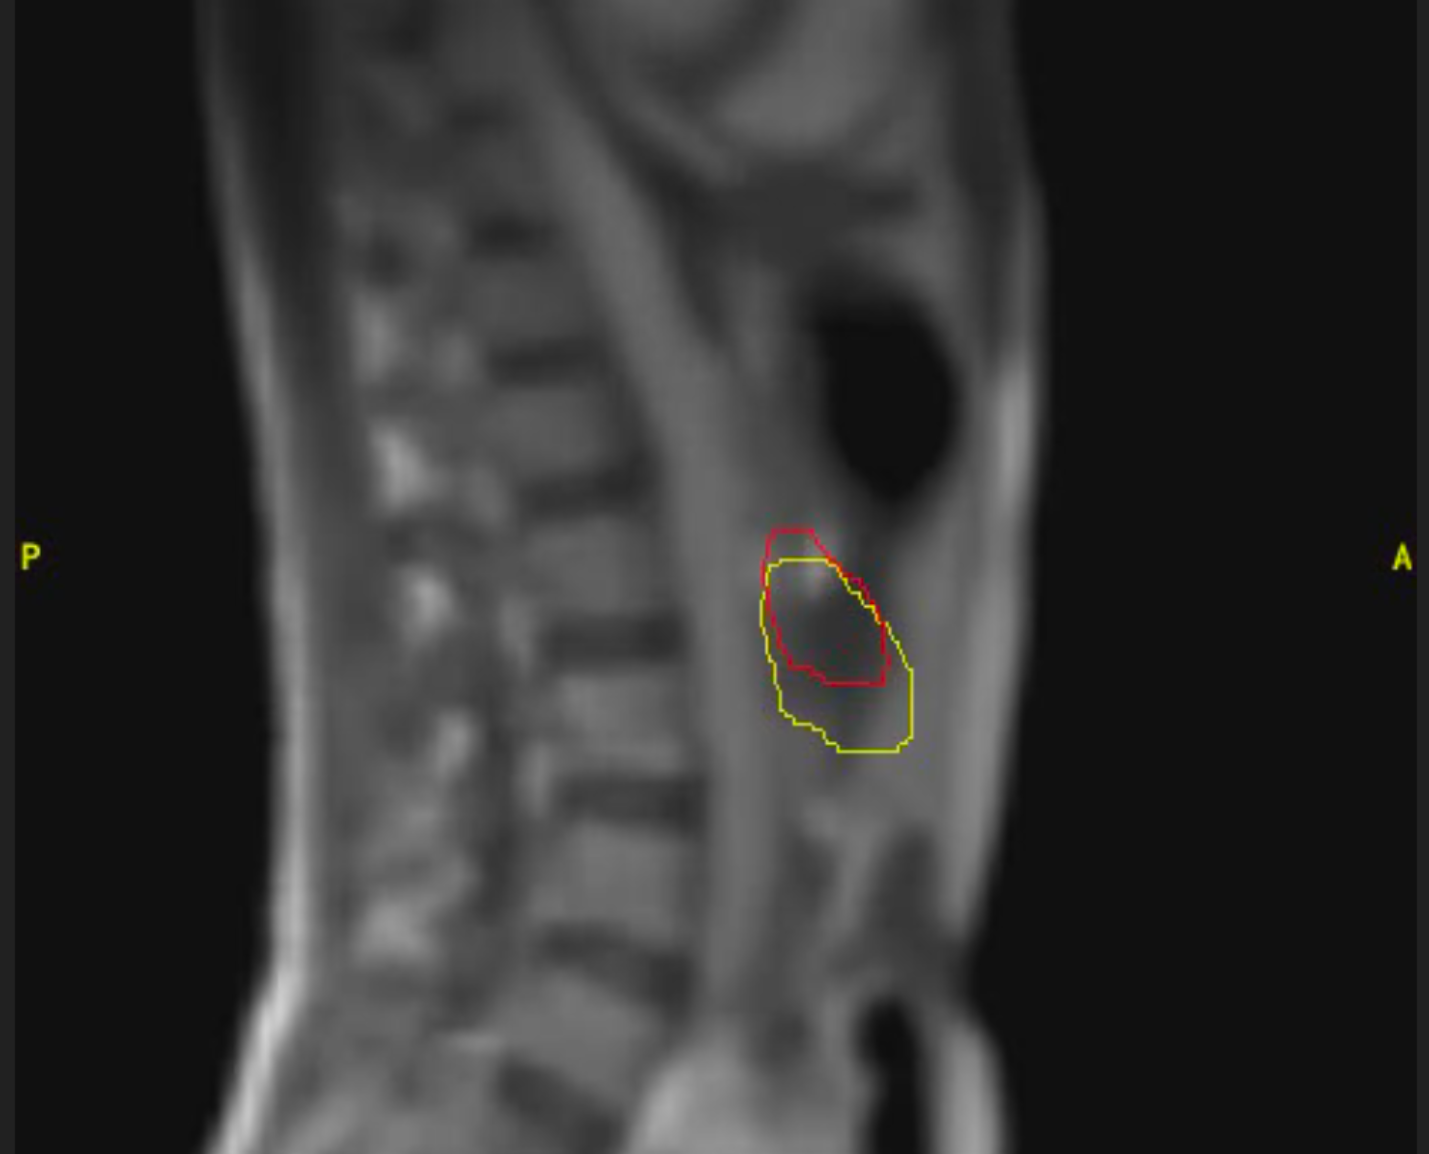

Cáncer de próstata

Varón de 85 años con diagnóstico de adenocarcinoma de próstata de bajo riesgo. Recibe tratamiento radioterápico con intención curativa en Acelerador Lineal con Resonancia (MRIdian): 5 fracciones en 5 días. Buena tolerancia, no efectos adversos destacables salvo ligero escozor al orinar autolimitado durante una semana.

Imagen 1

Imagen 2

Imagen 3